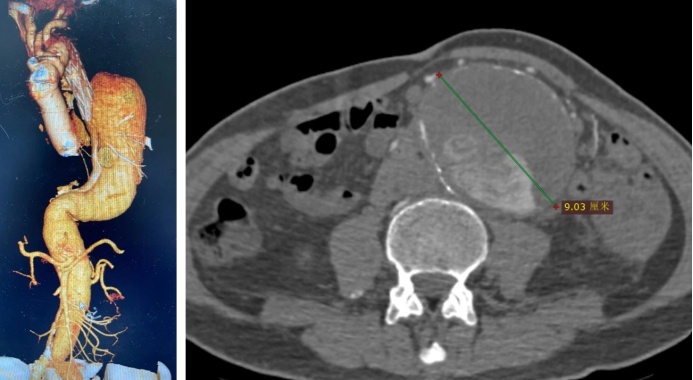

82岁的黄老十五年前,因突发A型主动脉夹层,在外院接受了“升主动脉-主动脉弓置换术”。近一年来黄老出现腰背部隐痛越来越明显,今年年初,CT检查时发现,残留的胸腹主动脉夹层已膨胀成直径9厘米的"定时炸弹",这位耄耋老人再次面临生死考验。

冯家烜带领血管外科治疗团队,对黄老的CT造影影像进行了三维重建,通过这个"血管地图",团队精准定位了主动脉破损处与要器官血管的"交叉路口"。但冯主任发现,如果堵住那些比牙签还细的脊髓供血血管(肋间动脉、腰动脉),有很高的截瘫风险。